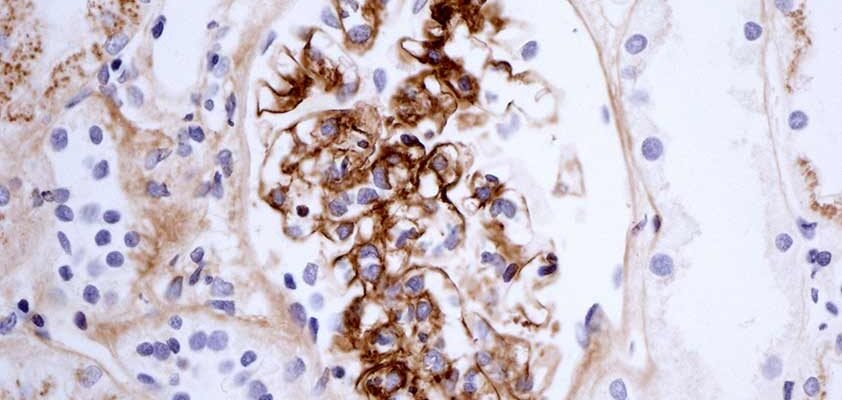

Хвороба Берже: Загадка Сучасної Медицини Хвороба Берже, також відома як IgA-нефропатія, хвилює медиків у всьому світі. Складна та, деколи, незрозуміла.